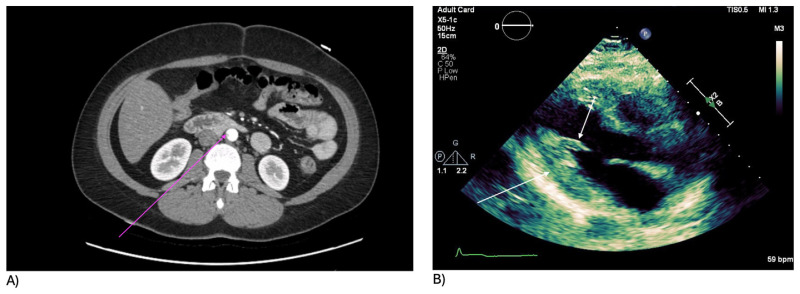

安非他明的使用与心血管风险的增加有关,如肺动脉高压、心律失常和动脉粥样硬化。一位47岁的女性在服用减肥药芬特明后发生了次心梗。她表现为胸痛、呼吸短促和呕吐。初步检查显示血压低,心率慢。随后的检查显示心脏酶水平升高,心电图显示ST段升高。冠状动脉造影显示右冠状动脉阻塞。她成功地接受了打开动脉的手术。该病例强调了与使用安非他明相关的心血管风险增加,即使在没有心脏疾病的个体中也是如此。研究和临床指南对于更好地预测、诊断和管理此类并发症至关重要。

Amphetamine use is associated with increasing rates of cardiovascular risks, such as pulmonary hypertension, arrhythmias, and atherosclerosis. A 47-year-old woman experienced an inferior MI after taking the weight loss drug phentermine. She presented with chest pain, shortness of breath, and vomiting. Initial examination showed low blood pressure and slow heart rate. Subsequent tests revealed elevated cardiac enzyme levels and ST elevations on EKG. A coronary angiogram showed a blockage in the right coronary artery. She underwent a successful procedure to open the artery. The case highlights the heightened cardiovascular risks associated with amphetamine use, even in individuals without existing heart conditions. Research and clinical guidelines are crucial for better prediction, diagnosis, and management of such complications.